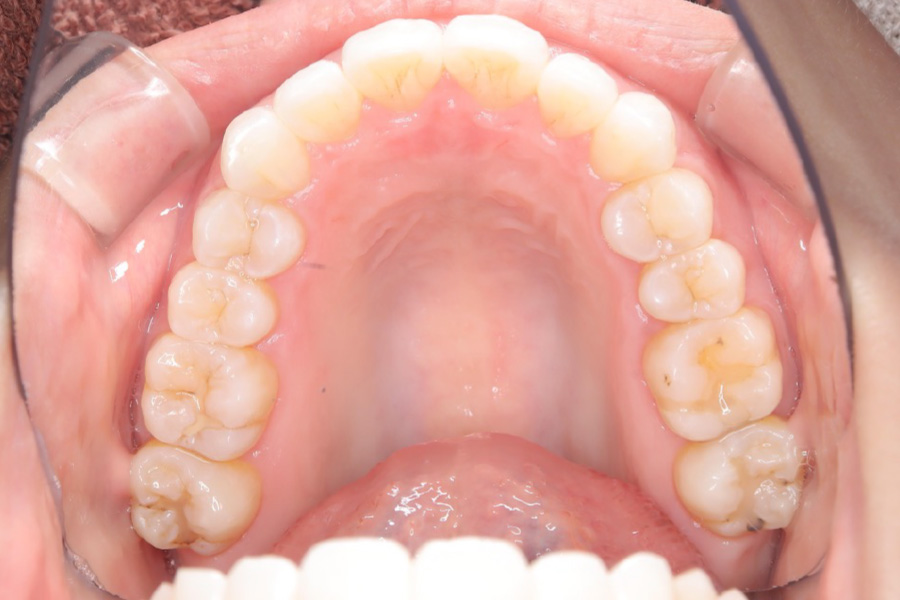

治療後

主訴 下の歯のガタつき、前歯の突出感が気になる

期間 2年半

治療内容 インビザライン矯正

非抜歯